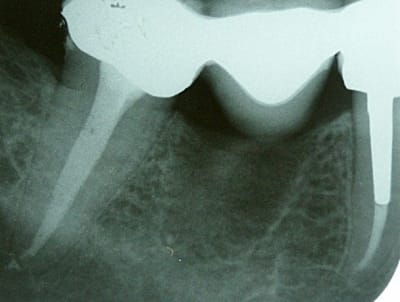

Ben voilà, j'ai fait l'endo aujourd'hui: digue, protaper, mac spadden, loupes orascoptic.

Je n'ai finalement trouvé qu'un seul gros canal dans cette fichue 47. J'ai du préparer à 45, tellement le foramen était gros. Il faisait bugger le root ZX.

Ci-jiont je vous file les radios.

La patiente est en or et a été super patiente pendant le soin.

t'as quand même eu du pot dans ton malheur,de n'avoir qu'un si gros canal,en tout cas bravo!